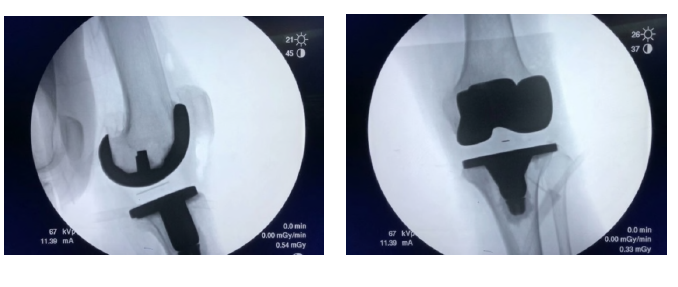

術中精準操作

術后X線片對比

手術實施順利

術后第4天, 周主任親自對該患者進行檢查和康復鍛煉, 膝關節可以完全伸直, 主動屈膝在100度以上。該患者對此次全膝關節置換手術的結果非常滿意。